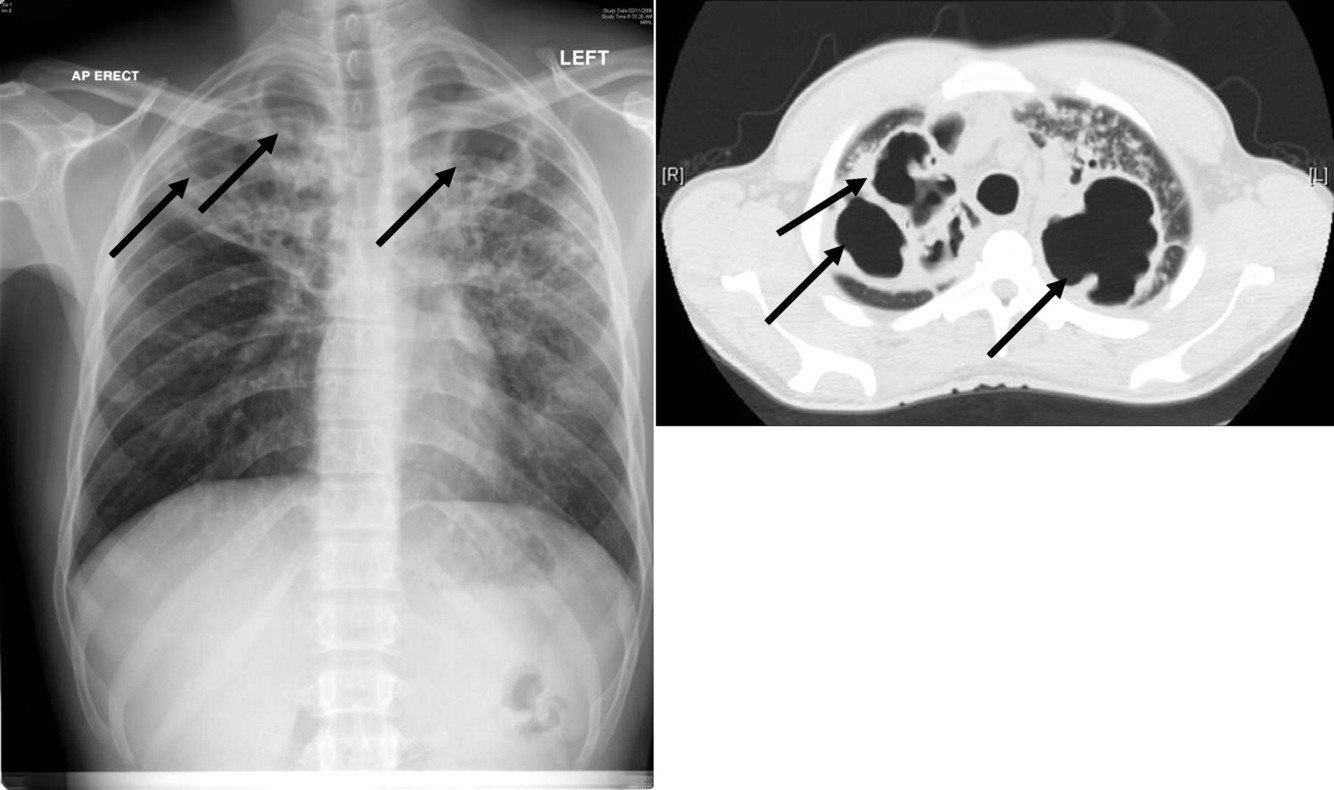

Organisms causing cavitating pneumonia (5)